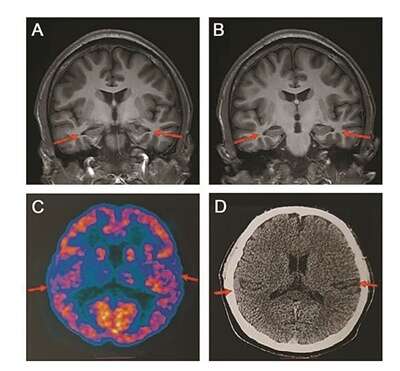

医院为患者做了多种检查,包括当前用于诊断阿尔兹海默症的最权威手段——脑脊液指标检测和PET扫描,患者还接受了多种量表测试。扫描影像等显示,患者存在轻度的脑萎缩等症状,部分脑脊液指标也存在异常,最终患者被临床诊断为阿尔兹海默症患者。